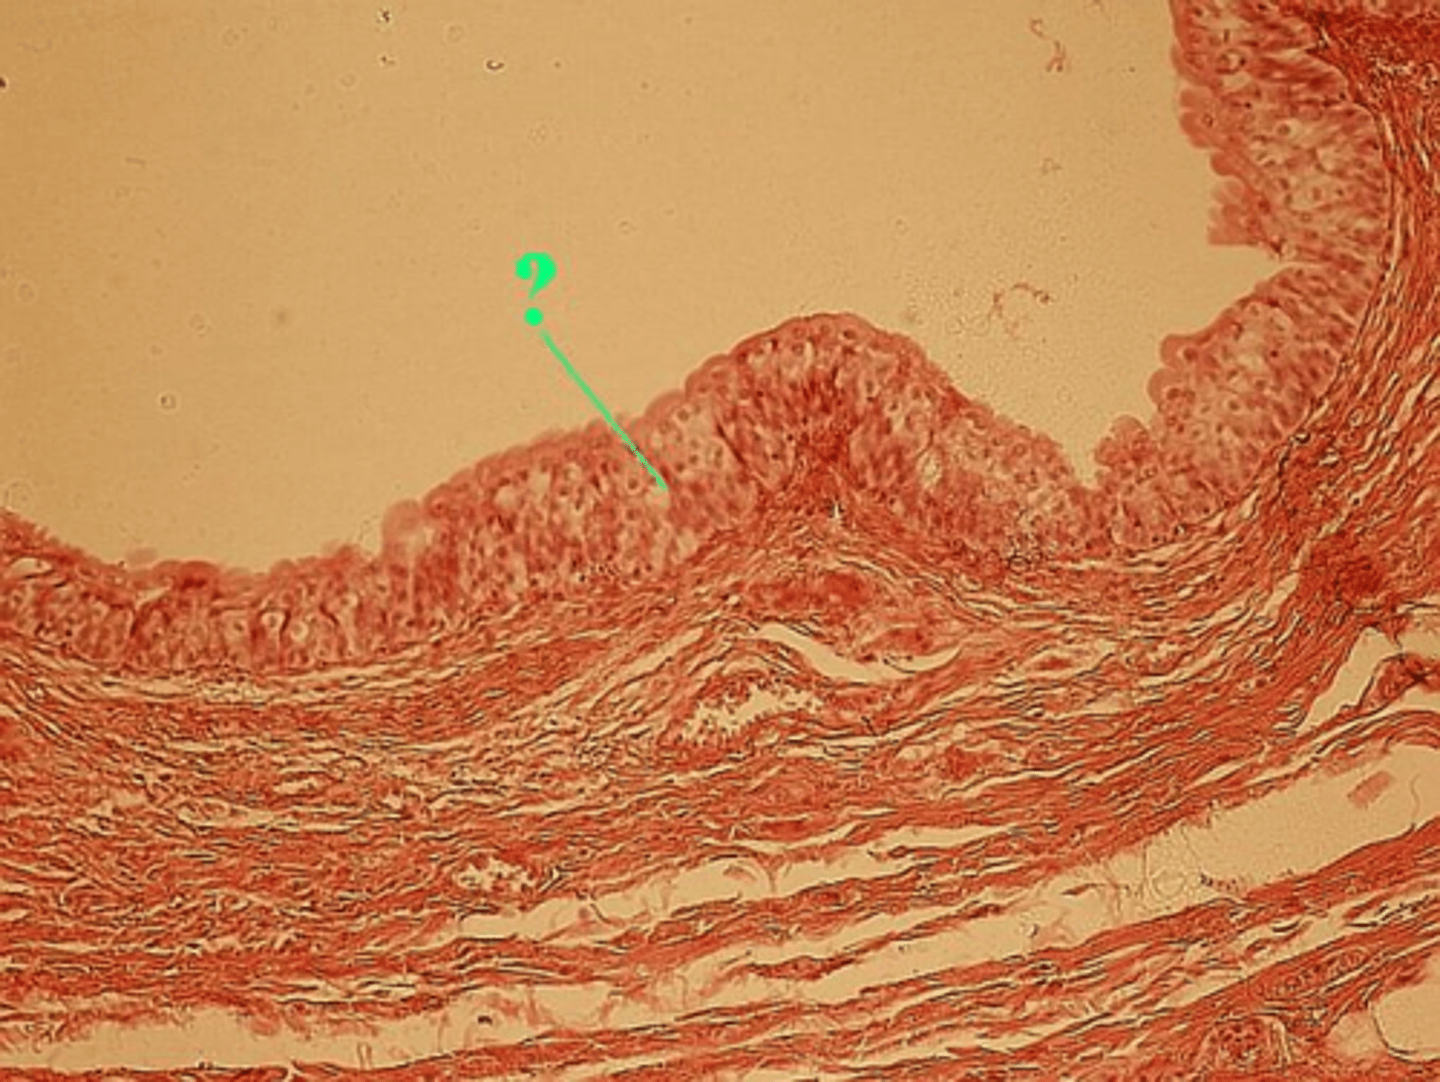

stratified columnar

What type of epithelium is present in this portion of the urethra?